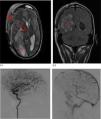

This is the case of a man with soft tissue septic shock due to Streptococcus pyogenes after trauma. Hematogenous spread with necrotizing fasciitis in the extremities (surgical resection) and meningitis with brain abscess (craniectomy and evacuation). Computed tomography (CT) with contrast: edema in the subcutaneous tissue of the left arm and muscle bellies, and a collection on the medial side of the right leg (Fig. 1, blue arrow). Right parietooccipital lobar cranial hematoma, vasogenic edema, and traumatic subarachnoid hemorrhage in the cisterns, with an increased mass effect (blurring of sulci and compression of the right lateral ventricle) (Fig. 2, orange box). Cranial MRI after clinical deterioration (Fig. 3): right occipitotemporal collection of 3.5 cm × 9 cm, irregular hypercaptating margins, and restriction (red stars) suggestive of brain abscess, with intraventricular pus, subfalcine herniation, right uncal herniation (red arrows), and subdural hematoma at the craniectomy site (red triangle).